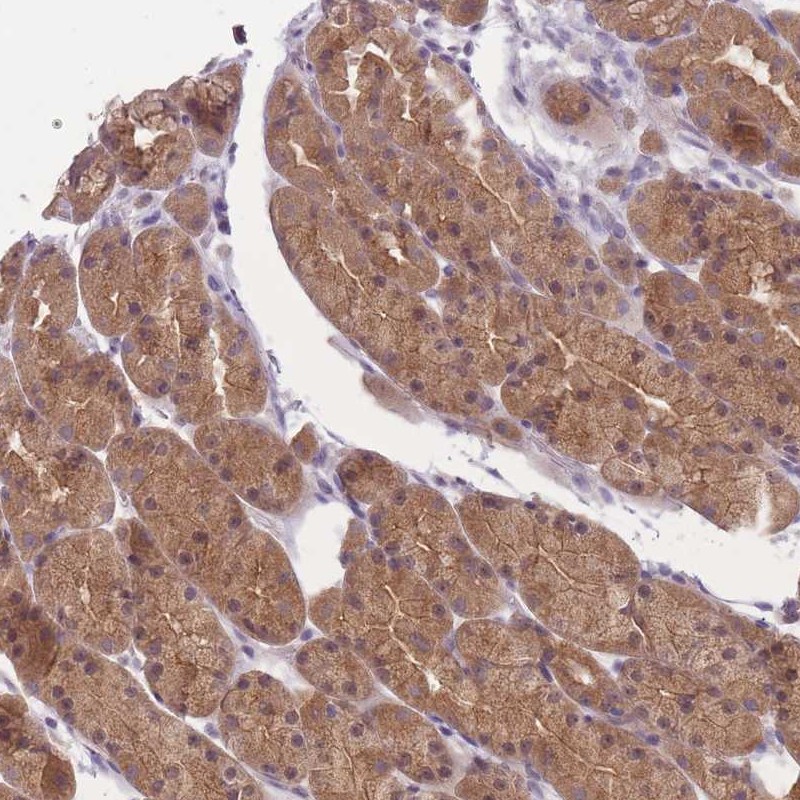

Immunohistochemical staining of human stomach, lower shows moderate cytoplasmic positivity in glandular cells.